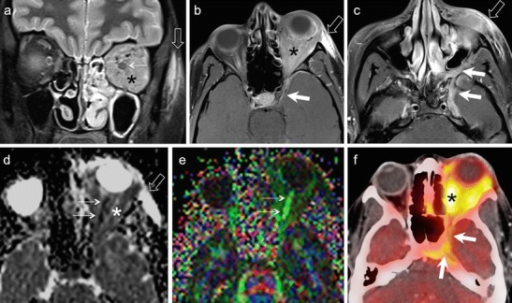

- CT: 골 침범, 석회화 평가

- MRI: 연조직 해상도 우수, 시신경 침범 평가

주요 안와종양 영상 소견